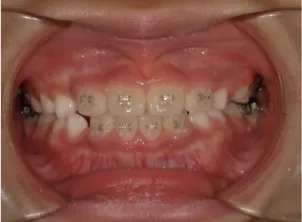

治療中④小2(8y2m)~小3(9y1m):QHとBHで拡大・アーチ形態の修正、ブラケットで前歯の並べ替えまで終了

| 行ったご提案・診断内容 | 成長期に行う治療と咬合治療をご提案 受け口用ファンクショナルアプライアンス(写真②③)からスタートし、小2以降で上下顎の拡大・歯列弓の形態修正・前歯の並べ直し(写真④)を行いその後、モノブロック(筋機能的咬合誘導)装置(写真⑤)へ移行し、受け口の再発予防と永久歯を適切な咬み合わせに誘導し、必要によりマルチブラケット法へ移行する治療方法を提案しました。 成長期治療(成長時期にお口の環境を整える治療) 2年生以降から 咬合治療 |

| 治療期間 | 12か月:受け口用ファンクショナルアプライアンス(写真②③) 12カ月:成長期治療の動的治療期間(写真④) 現在、成長の経過観察と咬合誘導中です(写真⑤~⑨) |